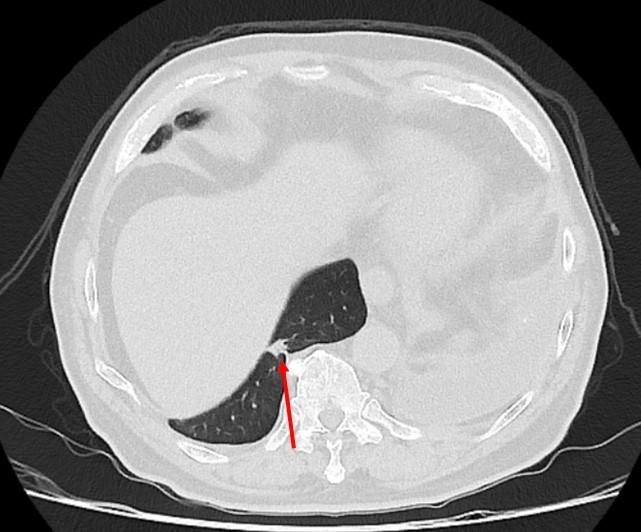

〔記者陳建志/台中報導〕75歲吳先生因肝臟細胞癌接受治療,沒想到又發現右下肺有一顆約1.2公分的腫瘤,因疑似肺癌轉介到胸腔及心臟血管外科,醫療團隊評估後決定進行手術切除,但因患者過去有車禍導致橫隔膜受傷,讓手術預期難度提高,決定採用健保給付的達文西機器人手術執行肺結節切除,順利切除腫瘤,並在術後第3天就出院返家休養。

仁愛長庚合作聯盟醫院胸腔及心臟血管外科主任廖啟耀表示,肺腫瘤手術在台灣十分普及且發達,但部分患者會讓醫師預期手術難度提高,其中以過去有過外傷經歷、曾接受過胸腔手術、肺臟腫瘤接受過放射性治療的病人最為常見,這類患者常見的手術困難度為解剖構造的改變,常因為胸腔發炎反應的影響,讓肺臟與周遭肋膜產生沾黏,同時血管的方向也更難分辨,對執行手術醫師而言是一項困難的挑戰。

廖啟耀指出,患者的橫隔膜如果和肺臟沾黏,手術空間將較為狹小,達文西機器人手術可提供穩定的操作及清晰的手術視野,這對於外科醫師在分沾黏上是如虎添翼,透過穩定且精細的操作,團隊將患者的橫隔膜與肺臟分離,並完成之後的肺節切除手術。